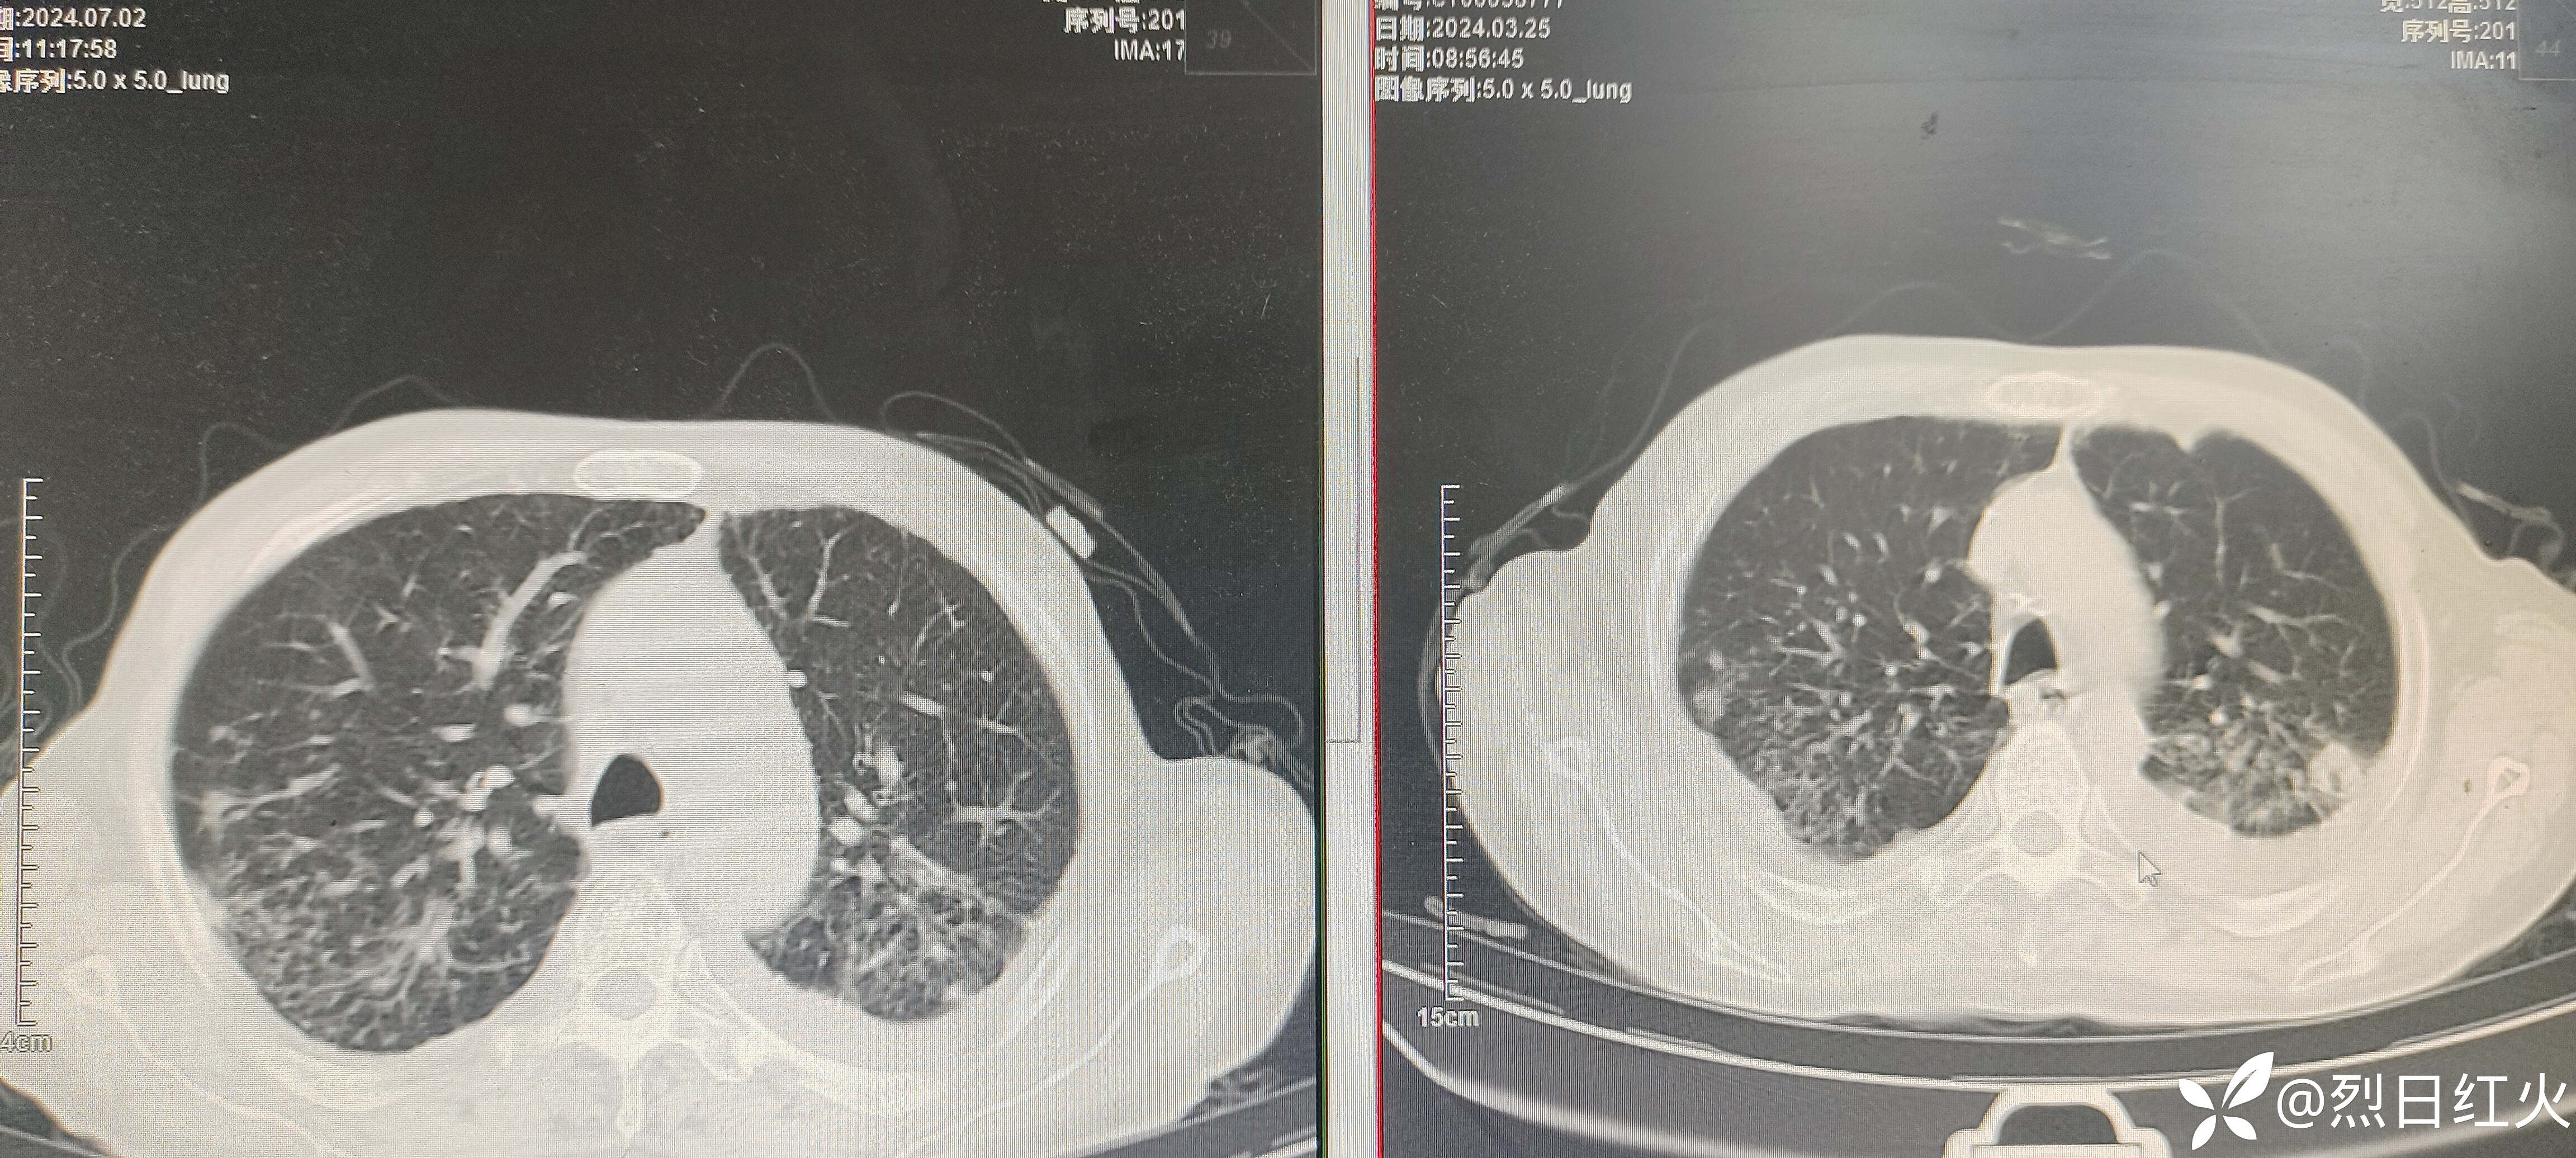

该病历患者入院后病情缓解,以后症状逐渐加重,治疗经过有不足之处望指正!2024-07-02复查胸部CT与2024-03-25胸部CT对比,病灶较前明显吸收。如下图:

患者经伏立康唑抗真菌治疗后症状及影像上均得到改善!目前出现面部,双手(裸露皮肤)发黑。考虑伏立康唑药物不良反应导致皮肤变色,光反应。鉴于患者情况是否停抗真菌药,还是继续当前剂量服用,或者减量服用,如减量减多少?请各位大咖,各位考师指点,谢谢!